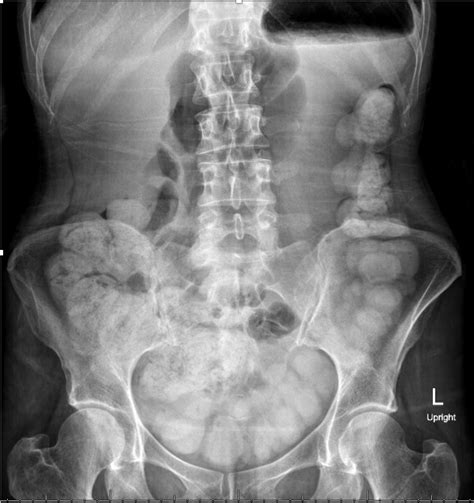

In the context of radiology, Moderate Colonic Stool Burden refers to a finding where the radiologist identifies a significant but not obstructive amount of fecal material throughout the colon. The term "moderate" is subjective and typically signifies that the intestine is not entirely empty, yet it does not necessarily suggest a state of pathological constipation or a complete bowel obstruction.

Imaging technology—such as X-rays—is excellent at picking up density. Because stool has a distinct appearance on these scans due to its density and trapped gas, it is easily identified. Radiologists use terms like "mild," "moderate," or "severe" to quantify how much of the colon is occupied by this material. In most asymptomatic individuals, this finding is considered an incidental, non-urgent observation.